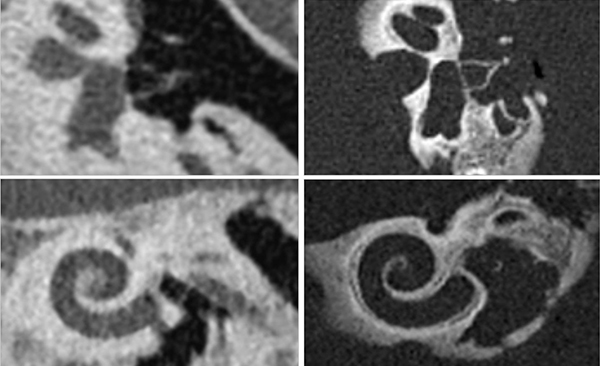

Photon-counting CTのプロトタイプによる研究は2014年から開始され,すでに100を超える論文が発表されている。また,NAEOTOM Alphaの臨床研究から多くの臨床画像も出てきている。分解能0.11mmの実現により,あぶみ骨や蝸牛などの微細な構造を従来CTと比べ非常に高精細に描出することができる。また,被ばく低減の効果も顕著で,副鼻腔を0.0063mSvという超低線量で撮影可能という報告もされている。

従来CT(左)とNAEOTOM Alpha(右)によるあぶみ骨と蝸牛の描出